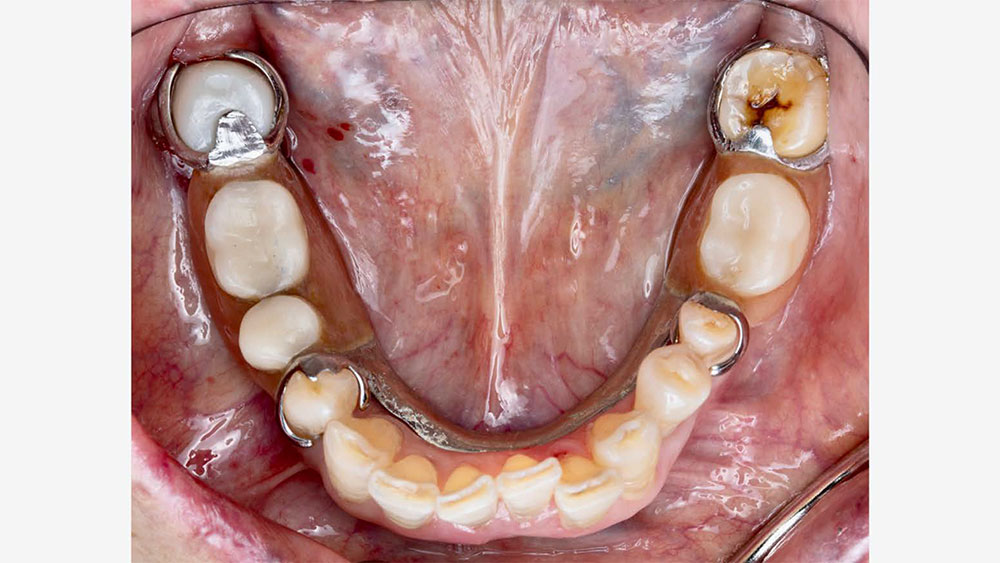

For existing partials, examine the occluding tooth contact, the position of the tongue, how the retentive and reciprocal arms are placed, and how it rests on the occlusal surface of the crown. Be sure to also examine the patient’s oral environment when the partial is removed, noting the spacing and the gingival region around the crown.

Partial-over-original-crown

Partial over original crown

Quality Control at Glidewell

As part of the lab’s quality control process, Glidewell supplies a 3D-printed model and a removable pattern of the partial along with the final crown. This is done in order to check the path of insertion, confirm proper seating and verify engagement with the crown. The photos below show an example of a 3D partial duplicate and model that were supplied with a final crown.